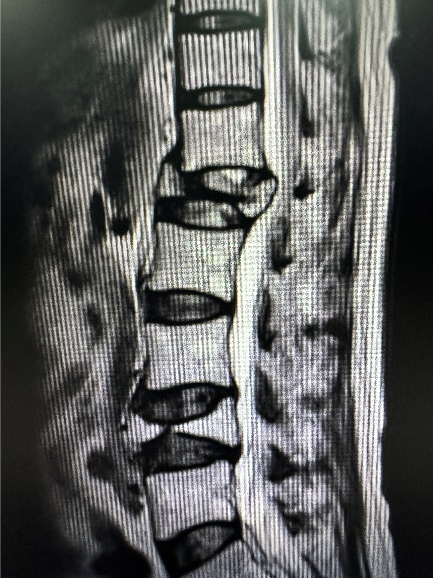

高龄老人腰椎骨折的治疗之路

72岁的李大爷2年前腰椎骨折,当时因畏惧手术治疗,选择卧床养病保守治疗,却不想留下了严重的后遗症。2年来,洪爷爷双下肢麻木、疼痛症状逐渐加重,行走困难。后选择在我院行手术治疗。

结合影像学资料,在徐永清教授指导下,科室召开病例讨论会,在于家属充分沟通后制定最终手术方案:“后路椎板减压、病椎4级截骨、钛笼植骨融合内固定术”。

此技术的优势显而易见,术后不仅恢复快,患者康复周期大大缩短,钛笼稳定性强,能够有效支持患者的脊椎结构,特殊材料的使用提高了植骨融合的可能性。术后洪爷爷安返病,现已能正常下地行走,双下肢麻木、疼痛症状明显缓解,生活质量得到明显提升。